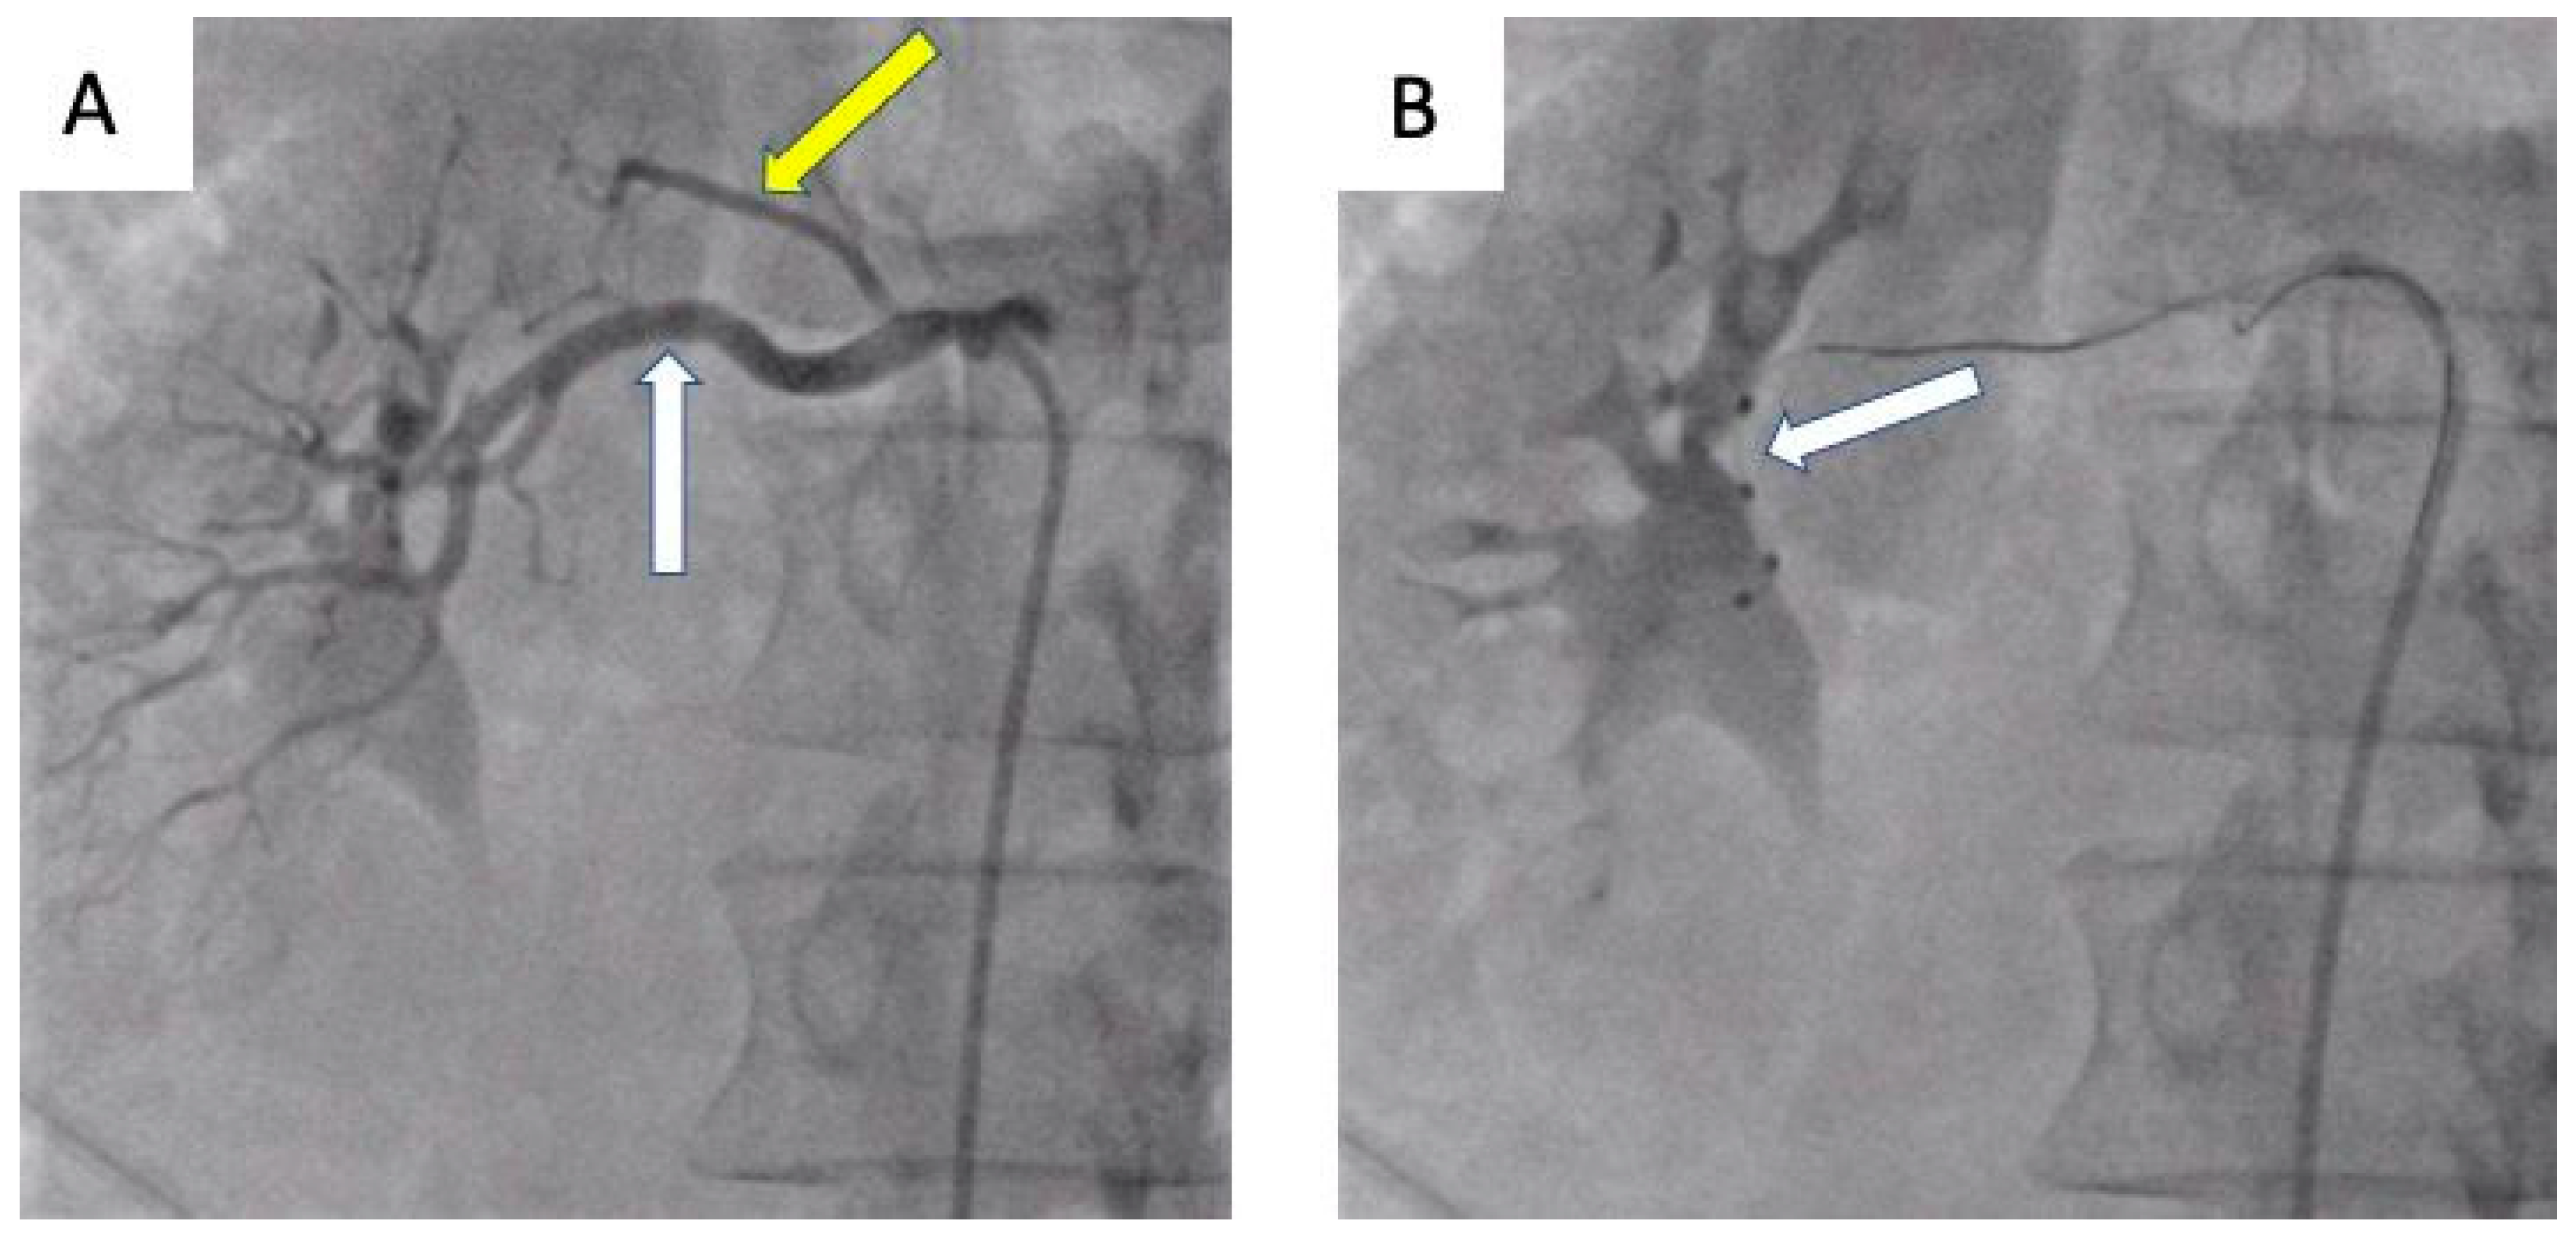

- Możeńska, O.; Rosiak, M.; Gziut, A.; Gil, R.J.; Kosior, D.A. First-in-man experience with renal denervation of multiple renal arteries in a patient with solitary kidney and resistant hypertension. Pol. Arch. Intern. Med. 2017, 127, 60–62. [Google Scholar] [CrossRef]

- Tokarek, T.; Rajtar-Salwa, R.; Rzeszutko, Ł.; Bartuś, S. Long-term benefit of redo sympathetic renal denervation in a patient with resistant hypertension. Postep. Kardiol. Inter. 2021, 17, 239–241. [Google Scholar] [CrossRef] [PubMed]

- Atas, H.; Durmus, E.; Sunbul, M.; Mutlu, B. Successful accessory renal artery denervation in a patient with resistant hypertension. Heart Views 2014, 15, 19–21. [Google Scholar] [PubMed]

- Bertoldi, L.; Latib, A.; Piraino, D.; Regazzoli, D.; Sticchi, A.; Pizzetti, G.; Camici, P.G.; Colombo, A. Renal denervation in a patient with two renal accessory arteries: A case report. Blood Press 2013, 22, 325–328. [Google Scholar] [CrossRef] [PubMed]

- de Leon-Martinez, E.P.; Garza, J.A.; Azpiri-Lopez, J.R.; Dillon, K.N.; Salazar, L.O.; Canepa-Campos, F.; Rousselle, S.D.; Tellez, A. Safety and Clinical Outcome of the Delivery of Radiofrequency Nerve Ablation Therapy in a Renal Artery of Unusual Anatomy. High Blood Press Cardiovasc. Prev. 2015, 22, 445–448. [Google Scholar] [CrossRef]